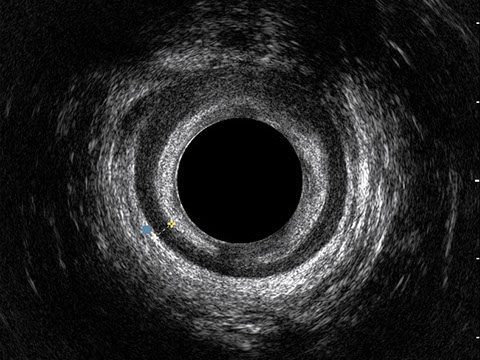

L’ecografia transanale è un esame diagnostico per immagini che consiste nell’introduzione di un trasduttore ad ultrasuoni. Le immagini qualitativamente migliori del canale anale sono ottenute usando un trasduttore rotante, montato in un manipolo rigido, che fornisce un’immagine a 360°. Con le apparecchiature più moderne è anche possibile ottenere immagini tridimensionali.

L’ecografia transanale permette di distinguere la sottomucosa che riveste il canale anale, lo sfintere anale interno, e lo sfintere anale esterno.